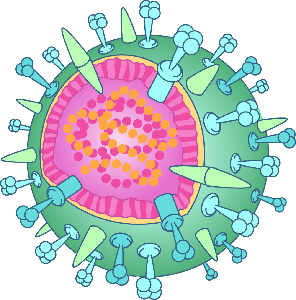

Detailreiche Fotografien aus der medizinischen Praxis ergänzen die Texte; moderne, genaue,

wissenschaftliche Zeichnungen geben Einblick in die Anatomie und die Funktion der Lunge und

anderer Organe.